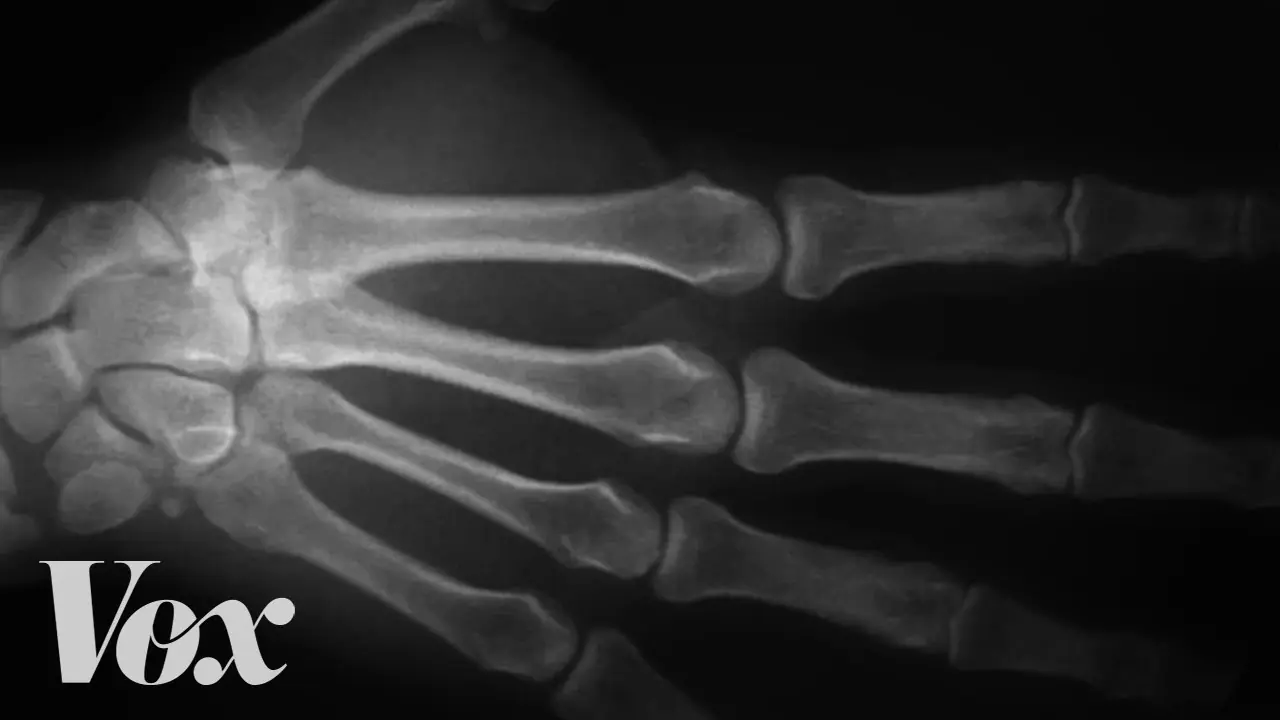

Unsettling Simulation Shows What Really Happens When You Crack Your Knuckles

Cracking your knuckles is a habit many people have. Some do it out of boredom, others say it helps relieve tension in their fingers. While many people have heard warnings that this habit could damage the joints or cause arthritis, scientists have spent years trying to understand what actually happens inside the body when that familiar “pop” sound occurs.

Recent simulations and imaging studies have revealed fascinating details about the process happening inside your joints when you crack your knuckles.

Your finger joints contain a slippery substance called synovial fluid, which helps lubricate the joint and allows bones to move smoothly against each other. This fluid also contains small amounts of dissolved gases such as nitrogen and carbon dioxide.

When you stretch or pull your fingers to crack a knuckle, the joint surfaces suddenly move apart. This increases the space inside the joint and causes the pressure in the synovial fluid to drop rapidly. As the pressure decreases, gas bubbles quickly form inside the fluid, creating the cracking sound.

In a well-known study published in the journal PLOS ONE, researchers used real-time MRI imaging to watch a finger joint while it was being cracked. They found that the cracking occurs in less than a second when a cavity (a gas-filled bubble) suddenly forms inside the joint fluid.

Interestingly, the bubble does not burst immediately as previously believed. Instead, it gradually dissolves back into the fluid over time.

This also explains why you usually cannot crack the same knuckle again right away. It typically takes around 20–30 minutes for the gas to dissolve and for another bubble to form.

Another study published in Scientific Reports created a mathematical model of knuckle cracking and concluded that the sound likely comes from the rapid collapse of a cavitation bubble, which releases energy and produces the familiar popping noise.

Simulations and medical imaging have finally given scientists a clear look at what happens when you crack your knuckles. The familiar popping sound is caused by rapid pressure changes inside the joint that create gas bubbles in the synovial fluid.